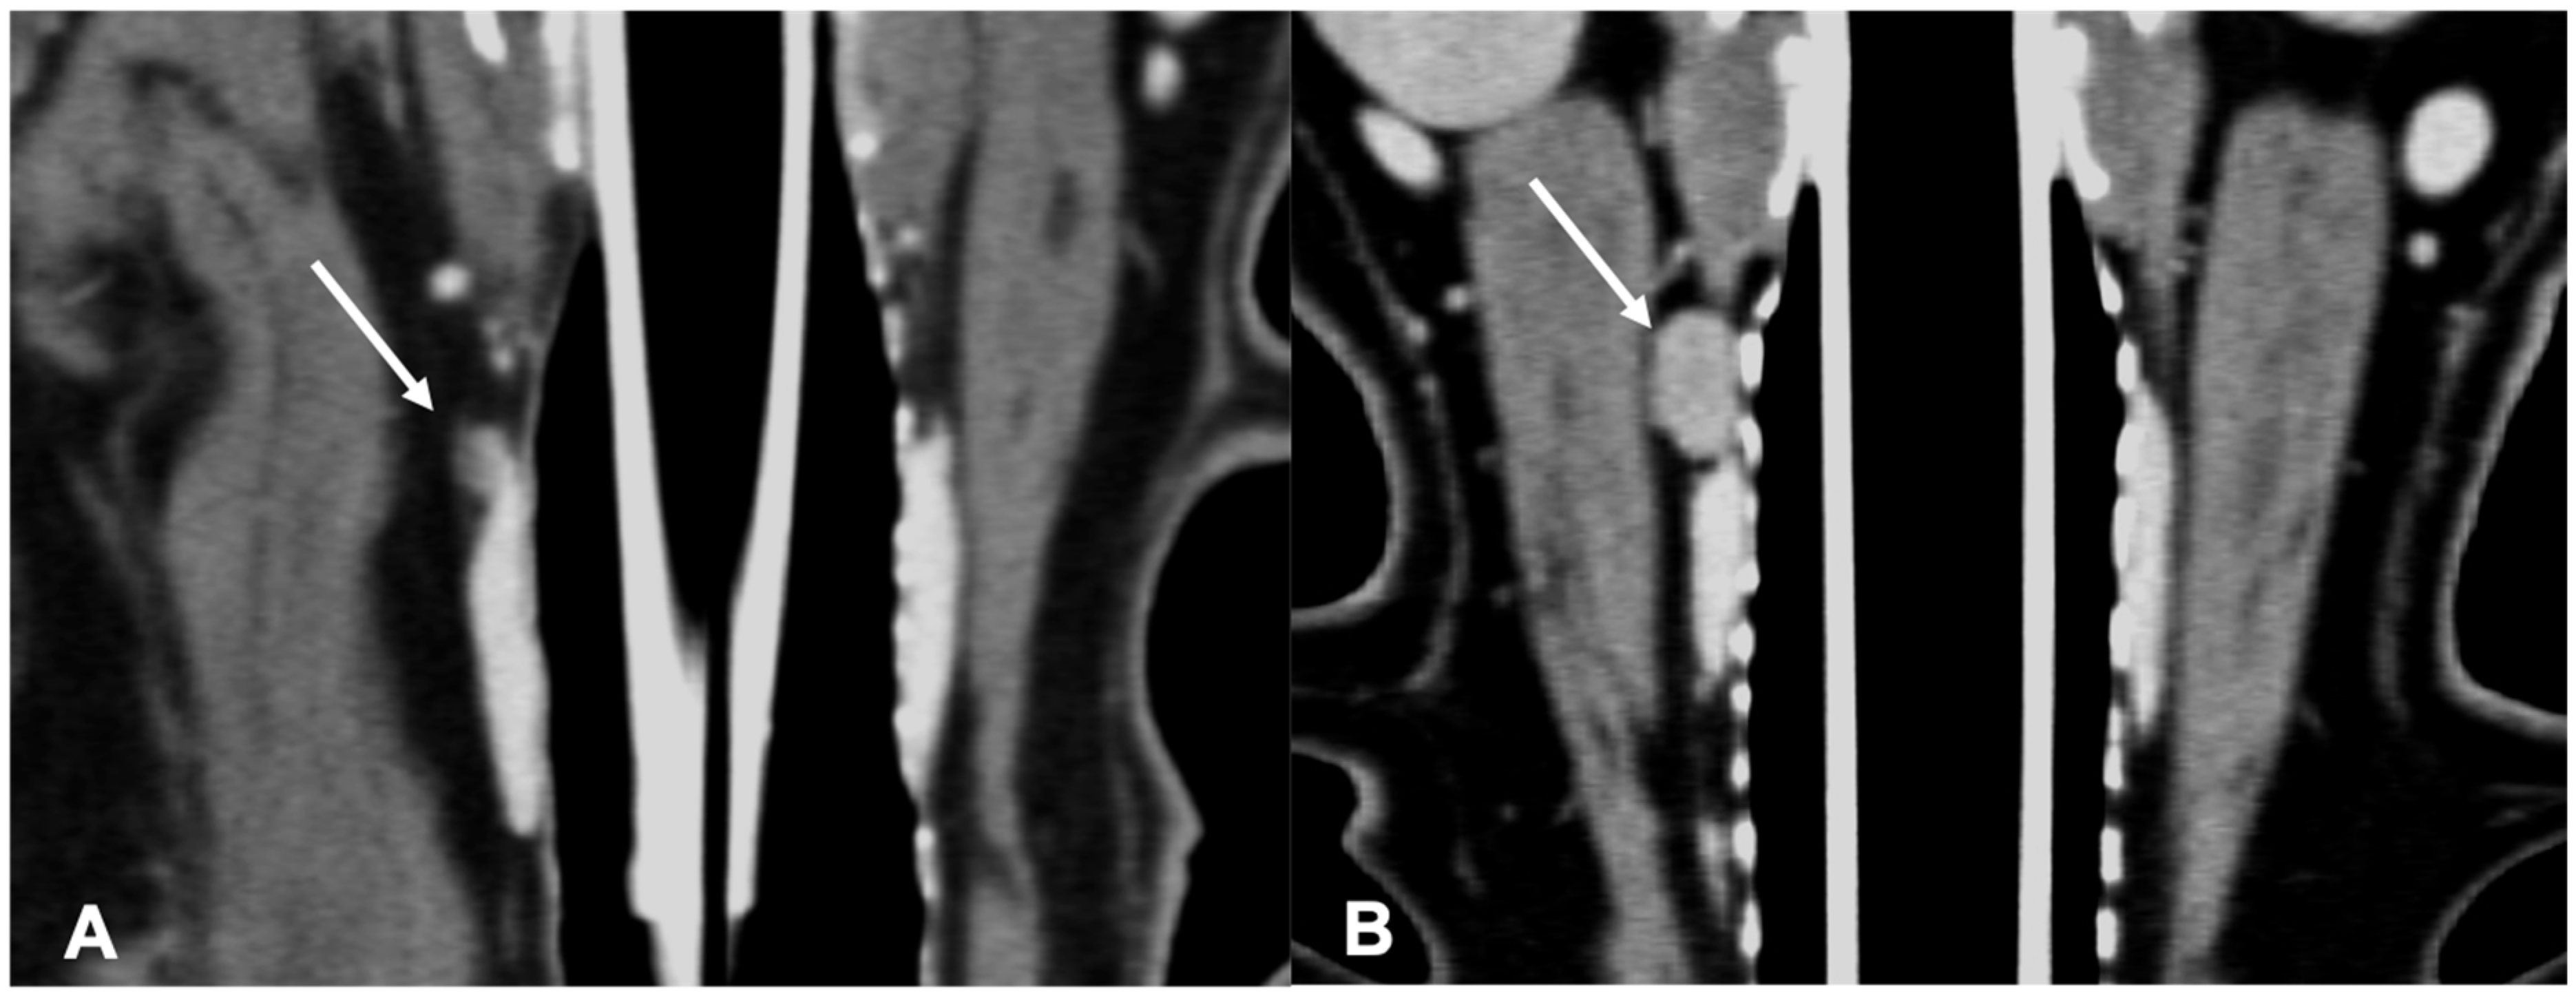

Figure 6.

CT appearance of parathyroid gland hyperplasia. Post-contrast dorsal (A) and right parasagittal (B) CT reconstruction of one dog with parathyroid gland hyperplasia (arrow) at the level of the right internal parathyroid. The parathyroid is ovoid-shaped and homogeneously contrast-enhancing. Note the marked difference in attenuation between the parathyroid (hypoattenuating) and the adjacent thyroid tissue.